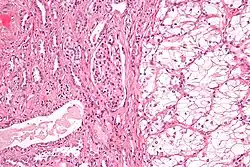

Bronchoalveolar carcinoma | Lepidic pattern of growth of tumor cells along the alveolar wall resembling butterfly sitting on fence. Normal alveoli is seen towards right side. | Category: Histopathology of bronchio-alveolar carcinoma | Bronchio-alveolar carcinoma |

![]() |